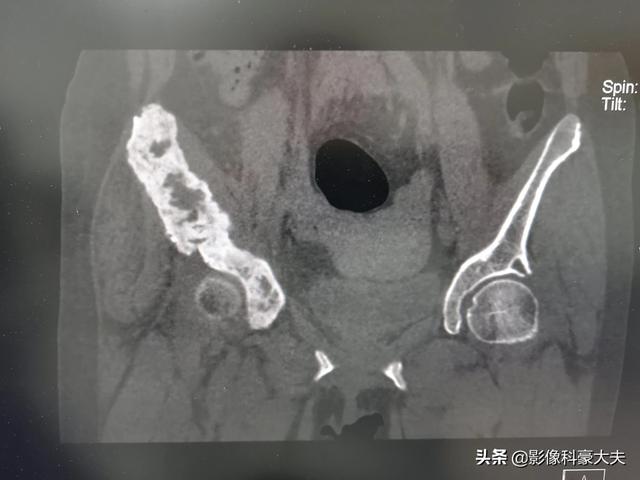

Ce patient souffrait de douleurs à la hanche et d'une suspicion de nécrose de la tête fémorale, ce qui a conduit à la détection de métastases osseuses au scanner du bassin et les examens complémentaires ont révélé un cancer du poumon à un stade avancé.

Les métastases osseuses se développent le plus souvent au niveau de la colonne lombaire, du bassin, des côtes, du crâne et du fémur.

Certains cancers sont plus susceptibles de métastaser dans les os. Comment savoir s'il y a eu métastase osseuse ? Le cancer est enclin à former des métastases et à détruire les tissus normaux, comme le cancer du poumon, le cancer du foie, le cancer du sein, le cancer de la prostate, etc. Dans notre travail, certains patients viennent consulter le médecin pour des douleurs osseuses, et le résultat de l'examen est une métastase osseuse du cancer. Métastases osseuses du cancer de la prostate (entourées en noir)